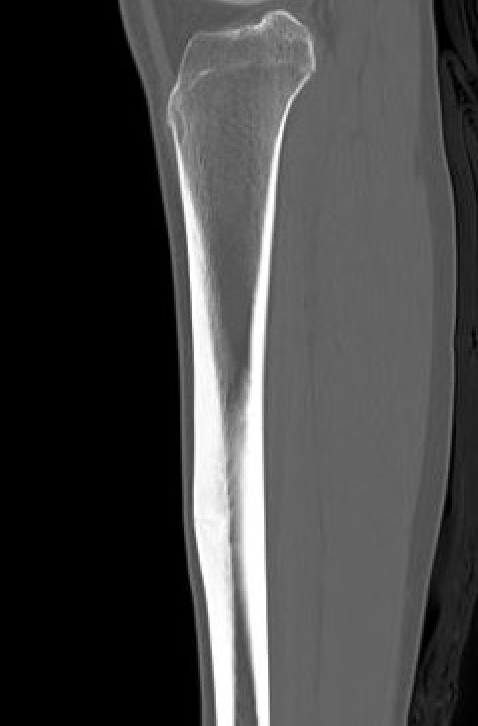

Xray

Cortical thickening

Look for "dreaded black line" - sign of fracture

Periosteal thickening with possible "dreaded black line"

Anterior cortical thickening with dreaded black line